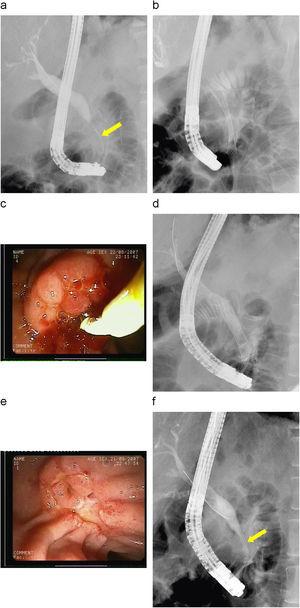

Figura 2. a) Estenosis de colédoco distal filiforme secundario a su pancreatitis crónica (flecha) con conducto cístico de implantación baja. Páncreas dorsal rellenado desde la papila minor (cabeza de flecha). b) Dilatación con balón de alta presión de 6mm de diámetro. c) Estenosis de 20mm de longitud en el colédoco distal con un calibre de menos de 2mm y dilatación de la vía biliar supraestenótica de 12mm. d) Prótesis migrada hacia colédoco; viéndose sólo parte de la malla metálica en el borde superior de la papila mayor. e) Prótesis metálica de 10×40mm que ha migrado hacia el colédoco. f) Papila mayor con tejido de granulación 2 meses después.

A los 2 meses, se realizó una nueva CPRE para valorar el recambio de la prótesis. Se pudo constatar que la prótesis había migrado hacia el colédoco, de tal manera que sólo se veía parcialmente la prótesis en la parte superior de la papila (figura 2d). En la imagen radiológica, se pudo comprobar la migración de la prótesis (figura 2e). Se intentó despegar la prótesis con asa de polipectomía, pinza de 3 patas, pinza de cuerpos extraños, pinza de biopsias, papilotomo con guía y luego mediante dilatación con balón entre la prótesis y el colédoco, sin que se consiguiera un resultado eficaz. Tras estas maniobras, se decidió introducir un balón de dilatación hidrostático dentro de la prótesis (CRE™ Wireguided 12-13,5-15mm Esophageal/Pyloric/Colonic 240cm, Boston Scientific Microvasive, Cork, Ireland), hincharlo a 3 atmósferas, traccionar de la prótesis hasta conseguir despegar la prótesis del colédoco y sacarla parcialmente al duodeno. Ahora, se extrajo con facilidad la prótesis mediante una pinza de cuerpos extraños.

A los 2 meses se revisaron el duodeno y el colédoco, y se encontró tejido de granulación en la zona donde se había adherido la prótesis (figura 2f) y un calibre de la estenosis muy superior a otras técnicas que alcanzaba los 8mm . Durante su seguimiento en 6 meses, presentó una bioquímica hepática normal sin evidenciar dilatación de la vía biliar mediante ecografía.